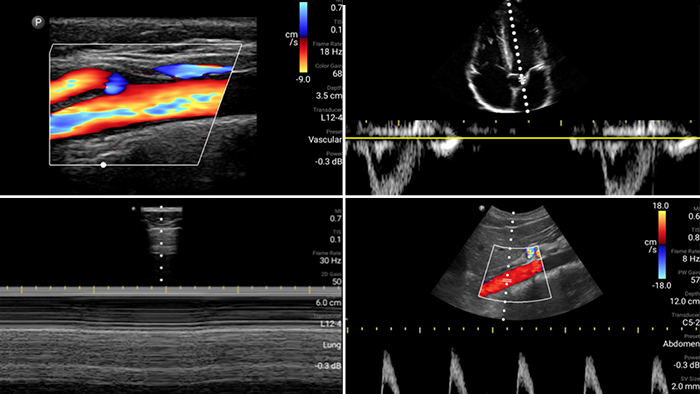

Błyskawiczne ocena, diagnoza i leczenie pacjentów dzięki badaniu POCUS.

Korzystanie z systemu Lumify może przyczynić się do szybszej oceny pacjentów oraz lepszego diagnozowania najczęstszych przyczyn duszności i innych chorób płuc

System pozwala wykonać wyraźne obrazowanie całego ciała, dzięki czemu można szybko uzyskać pełen obraz sytuacji i niezwłocznie podjąć niezbędne działania.

• Rozszerzony zakres częstotliwości roboczej od 4 do 1 MHz • Obrazowanie 2D, kolorowy Doppler, tryb M-mode, zaawansowana technika XRES oraz wielowymiarowe obrazowanie harmoniczne • Obrazowanie w wysokiej rozdzielczości do badań jamy brzusznej i serca: optymalizacja ustawień predefiniowanych obrazowania serca, badań położniczo-ginekologicznych, płuc, jamy brzusznej oraz protokołu FAST System Lumify pomaga ratować życie w warunkach przedszpitalnych